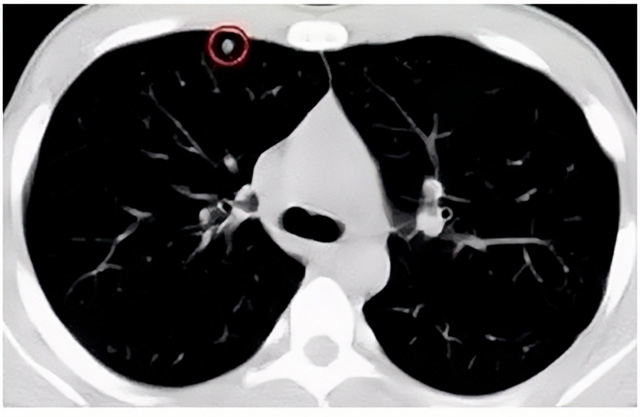

移动CT体检车可以检查肺结节发现早期肺癌

移动CT体检车可以做肺部检查。随着多层螺旋CT肺部低剂量扫描的临床应用,目前很多人选择肺部CT作为常规检查项目,较大地提高了肺结节的检出率。如果检查发现肺部有肺结节是磨玻璃型的,小于5mm的微小结节,大部分都是良性的。如果达到1CM以上的,很有可能有肺癌的机率。根据其内密度不同可分为磨玻璃结节、实性结节、部分实性结节。根据其大小可分为肺大结节、小结节和微小结节。如果是炎症性肺结节,几个月后复查有变化变小就不用做手术。如果CT再次复查结节没有变化,没有缩小就需要升级做病例检查。病理检查的确诊性是最高的。是有没患癌的标准。检查发现早的话,规范手术治疗,手术后5年的存活率很高的。肺癌这个要早发现早治疗。

现在的移动CT体检车的分辨率比X光高,CT扫描的图像越来越薄显像更清晰,检查更准确。得到了普及,肺结节的测出率很高的。但是太阳成集团tyc122cc告诉大家,肺结节不等于肺癌。虽然很多是良性,但是很多肺癌都是肺结节发展来的。 必须定期检查复查。磨玻璃结节,肺癌的机率较高。肺癌是恶性肿瘤病死率最高的。除了环境,遗传,等因素。吸烟,从事烟雾工作行业的人员比较危险。发病比例高。肺部疾病早发现早治疗,依旧是肺部疾病的治疗标准。